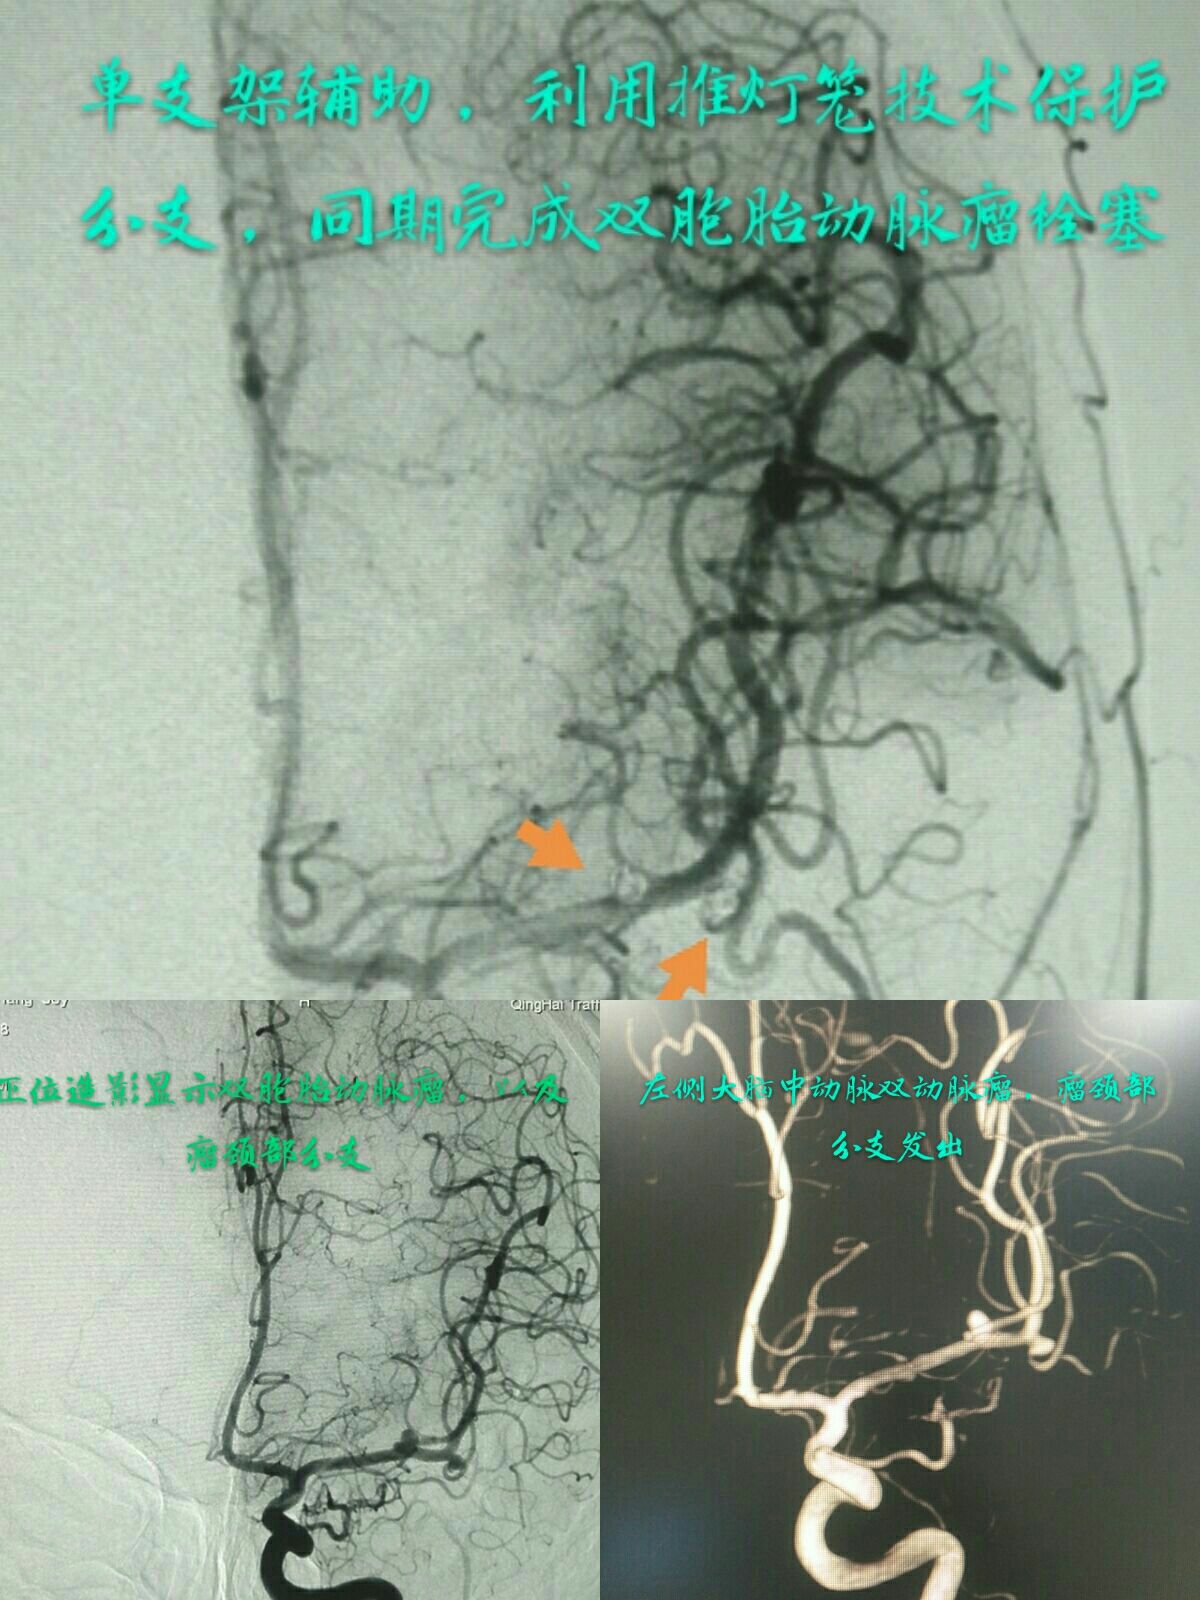

左侧大脑中动脉M2段双胞胎动脉瘤,用一个支架半释放方法栓塞远端动脉瘤,全释放后栓塞近段动脉瘤,术中用到了推“灯笼”技术